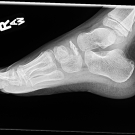

Laura R. Meidl; Natalie C. Stork, MD; Julia G. Harris, MD

An otherwise healthy 5-year-old boy presented to the pediatric rheumatology clinic for evaluation of a limp of 1 year’s duration. The patient also experienced intermittent right foot and ankle pain and...